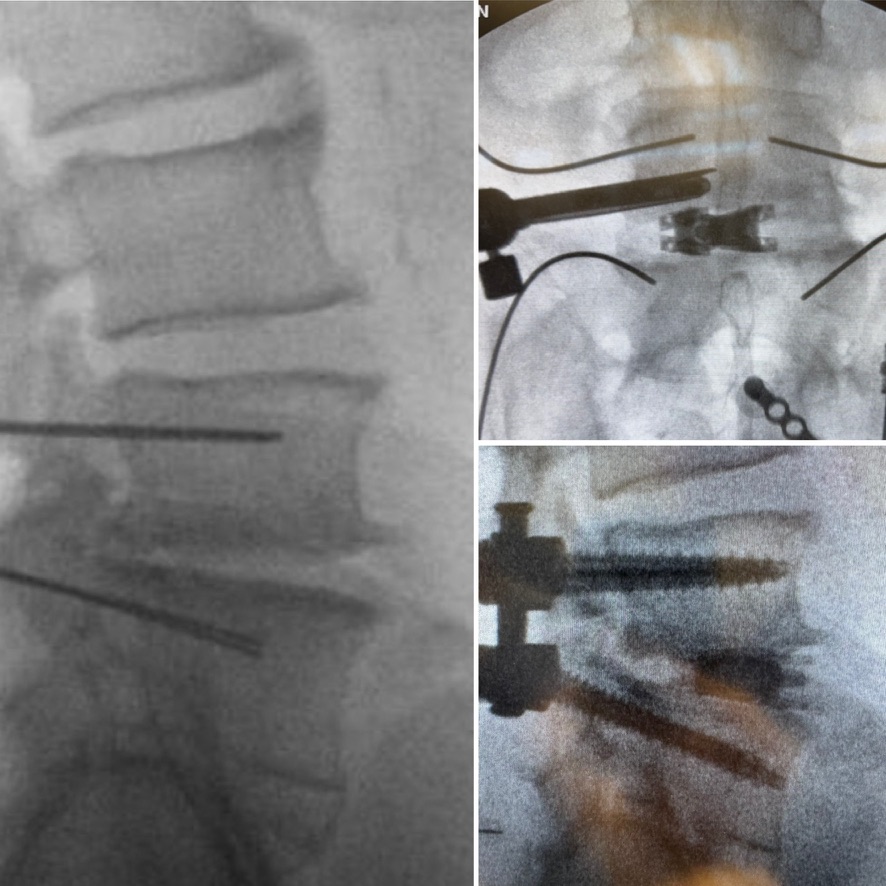

dualX®Slim transforms the fusion environment from insertion to spinal restoration by delivering a powerful dual-expanding implant through a minimally-invasive or endoscopic approaches. dualX®Slim has one of the smallest insertion profiles in the market while still expanding in both horizontal and vertical directions to provide an ALIF-sized final geometry with higher degrees of lordosis (8°, 12°, 15°, 18°*) through the patented trueLordosis™ technology.

Lateral expansion establishes stable footprint Large, center bone graft chamber for post-expansion grafting

20 mm Fully Expanded Width

Powerful vertical expansion restores disc height for decompression

Vertical expansion assists in direct and indirect decompression Multiple lordotic angles restore sagittal balance